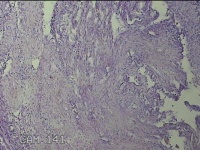

左卵巢囊肿

性别

女

年龄

47岁

临床诊断

左附件囊肿

一般病史

不规则阴道流血20余天。

标本名称

大体所见

灰白暗红色囊壁样组织4.3x1.3x0.3cm一块,表面光滑,因已切开,囊内容物已流失,囊壁厚0.1cm。

良性病变。